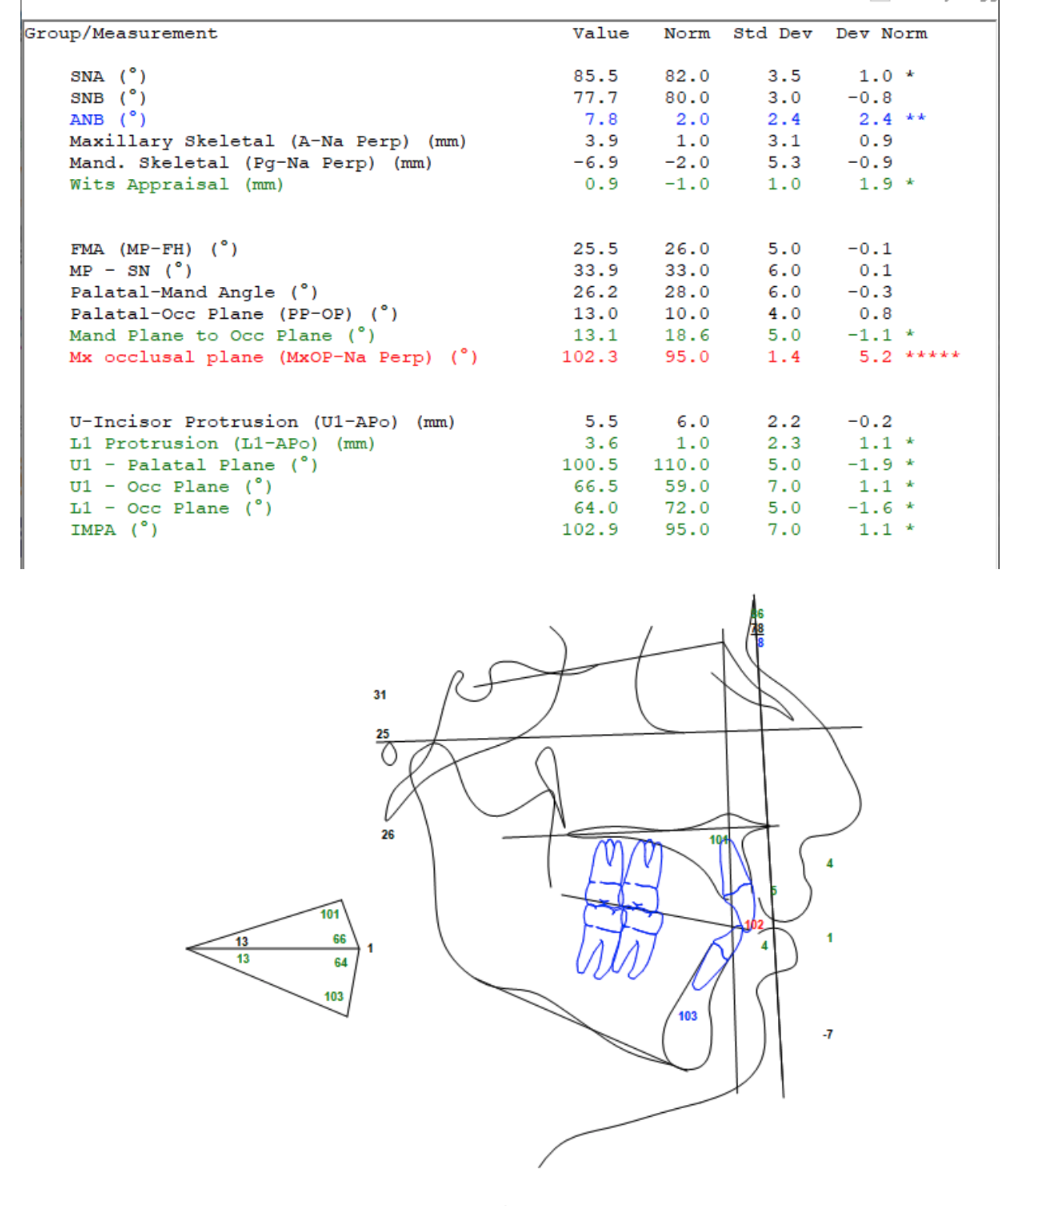

They are planning on doing a segmental 3-piece Lefort 1 which should give me about 5mm of expansion and 8mm of advancement, along with a CCW rotation of a few degrees (my dumbass forgot to ask how many) and a BSSO mandibular advancement of 12mm.

Feel free to ask any questions, also if any autists out there want to make comments about my scans, current appearance and my surgery plans then please do so.